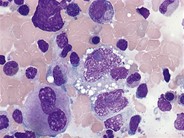

Anaplastic Large Cell Lymphoma ALK+ H&E

Category: Lymphoma: Mature T and NK cell lymphoproliferations > Mature T-cell Lymphomas > Anaplastic Large Cell Lymphoma, ALK positive

See reference case "Anaplastic Large Cell Lymphoma" for details.